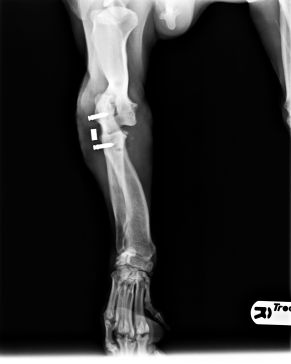

Enseguida nos hicimos cargo de él. Tras pasar una primera revisión veterinaria, decidimos trasladarlo a Madrid a una casa de acogida para tener una segunda opinión de un traumatólogo de nuestra confianza. El resultado fue el diagnóstico de luxación de codo en la pata delantera, y de fractura de huesos con luxación en la pata trasera. El problema es que estas lesiones tenían una antigüedad de unas 5 semanas, por lo que ya se había empezado a formar fibrosis y callo. Con todo ello se decidió dejar que la fractura siguiese su consolidación, y operar la luxación de codo, para intentar que recuperase completamente su funcionalidad.

Como se puede ver en las radiografías, con dos cirugías sobre la articulación, se consiguió la perfecta recolocación.